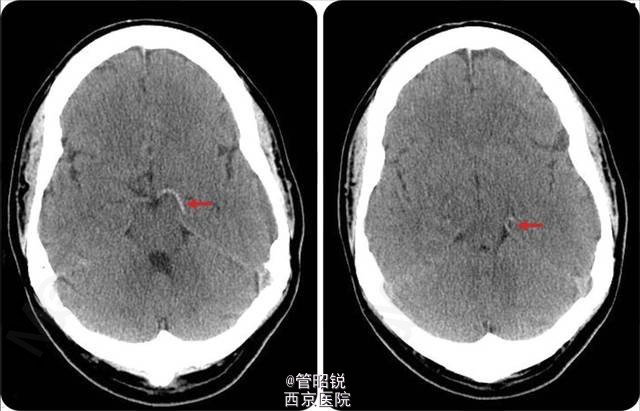

患者男性,38 岁,突发右侧肢体偏瘫、偏身感觉障碍及偏盲。头颅 CT 显示左侧大脑后动脉高密度征 (Hyperdense posterior cerebral artery sign,HPCAS)(见图 1)。CTA 显示左侧大脑后动脉闭塞(见图 2)。MRI 显示左侧大脑后动脉梗塞。经食管超声心动图检查可见一房间隔瘤和卵圆孔未闭。 患者予抗血小板聚集治疗。HPCAS 一直被认为是大脑后动脉区域急性梗塞的标志性征象。急性卒中后行头颅 CT 识别 HPCAS 有助于大脑后动脉分支梗塞的诊断与治疗。Neurology 杂志